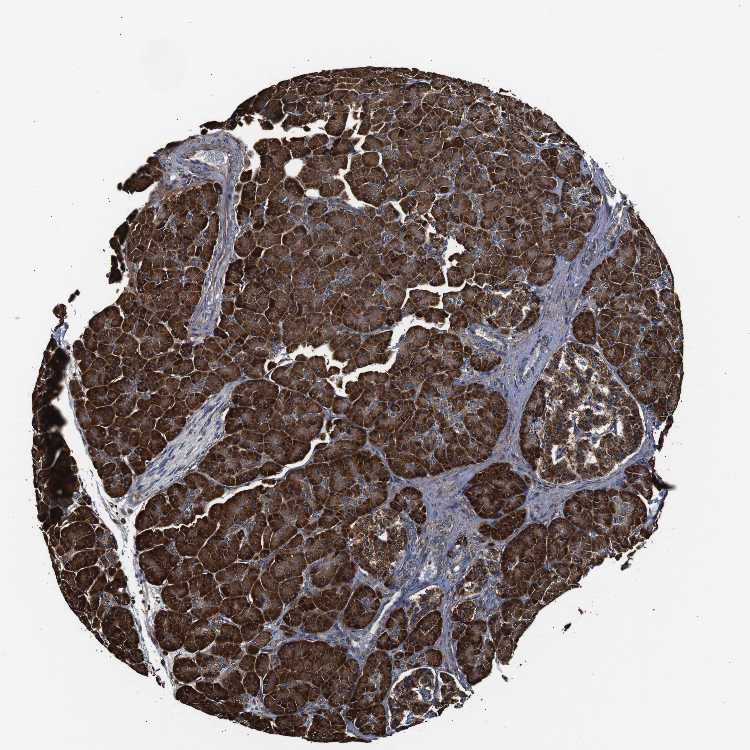

PANCREAS - Antibody stainingi

Antibody staining in the annotated cell types in the current human tissue is reported as not detected, low, medium, or high, based on conventional immunohistochemistry profiling in selected tissues. This score is based on the combination of the staining intensity and fraction of stained cells.

Each image is clickable and will lead to virtual microscopy that enables deeper exploration of all samples and also displays staining intensity scores, fraction scores and subcellular localization as well as patient and tissue information for each sample.

Antibody HPA012616

Exocrine glandular cells High

Pancreatic endocrine cells Medium